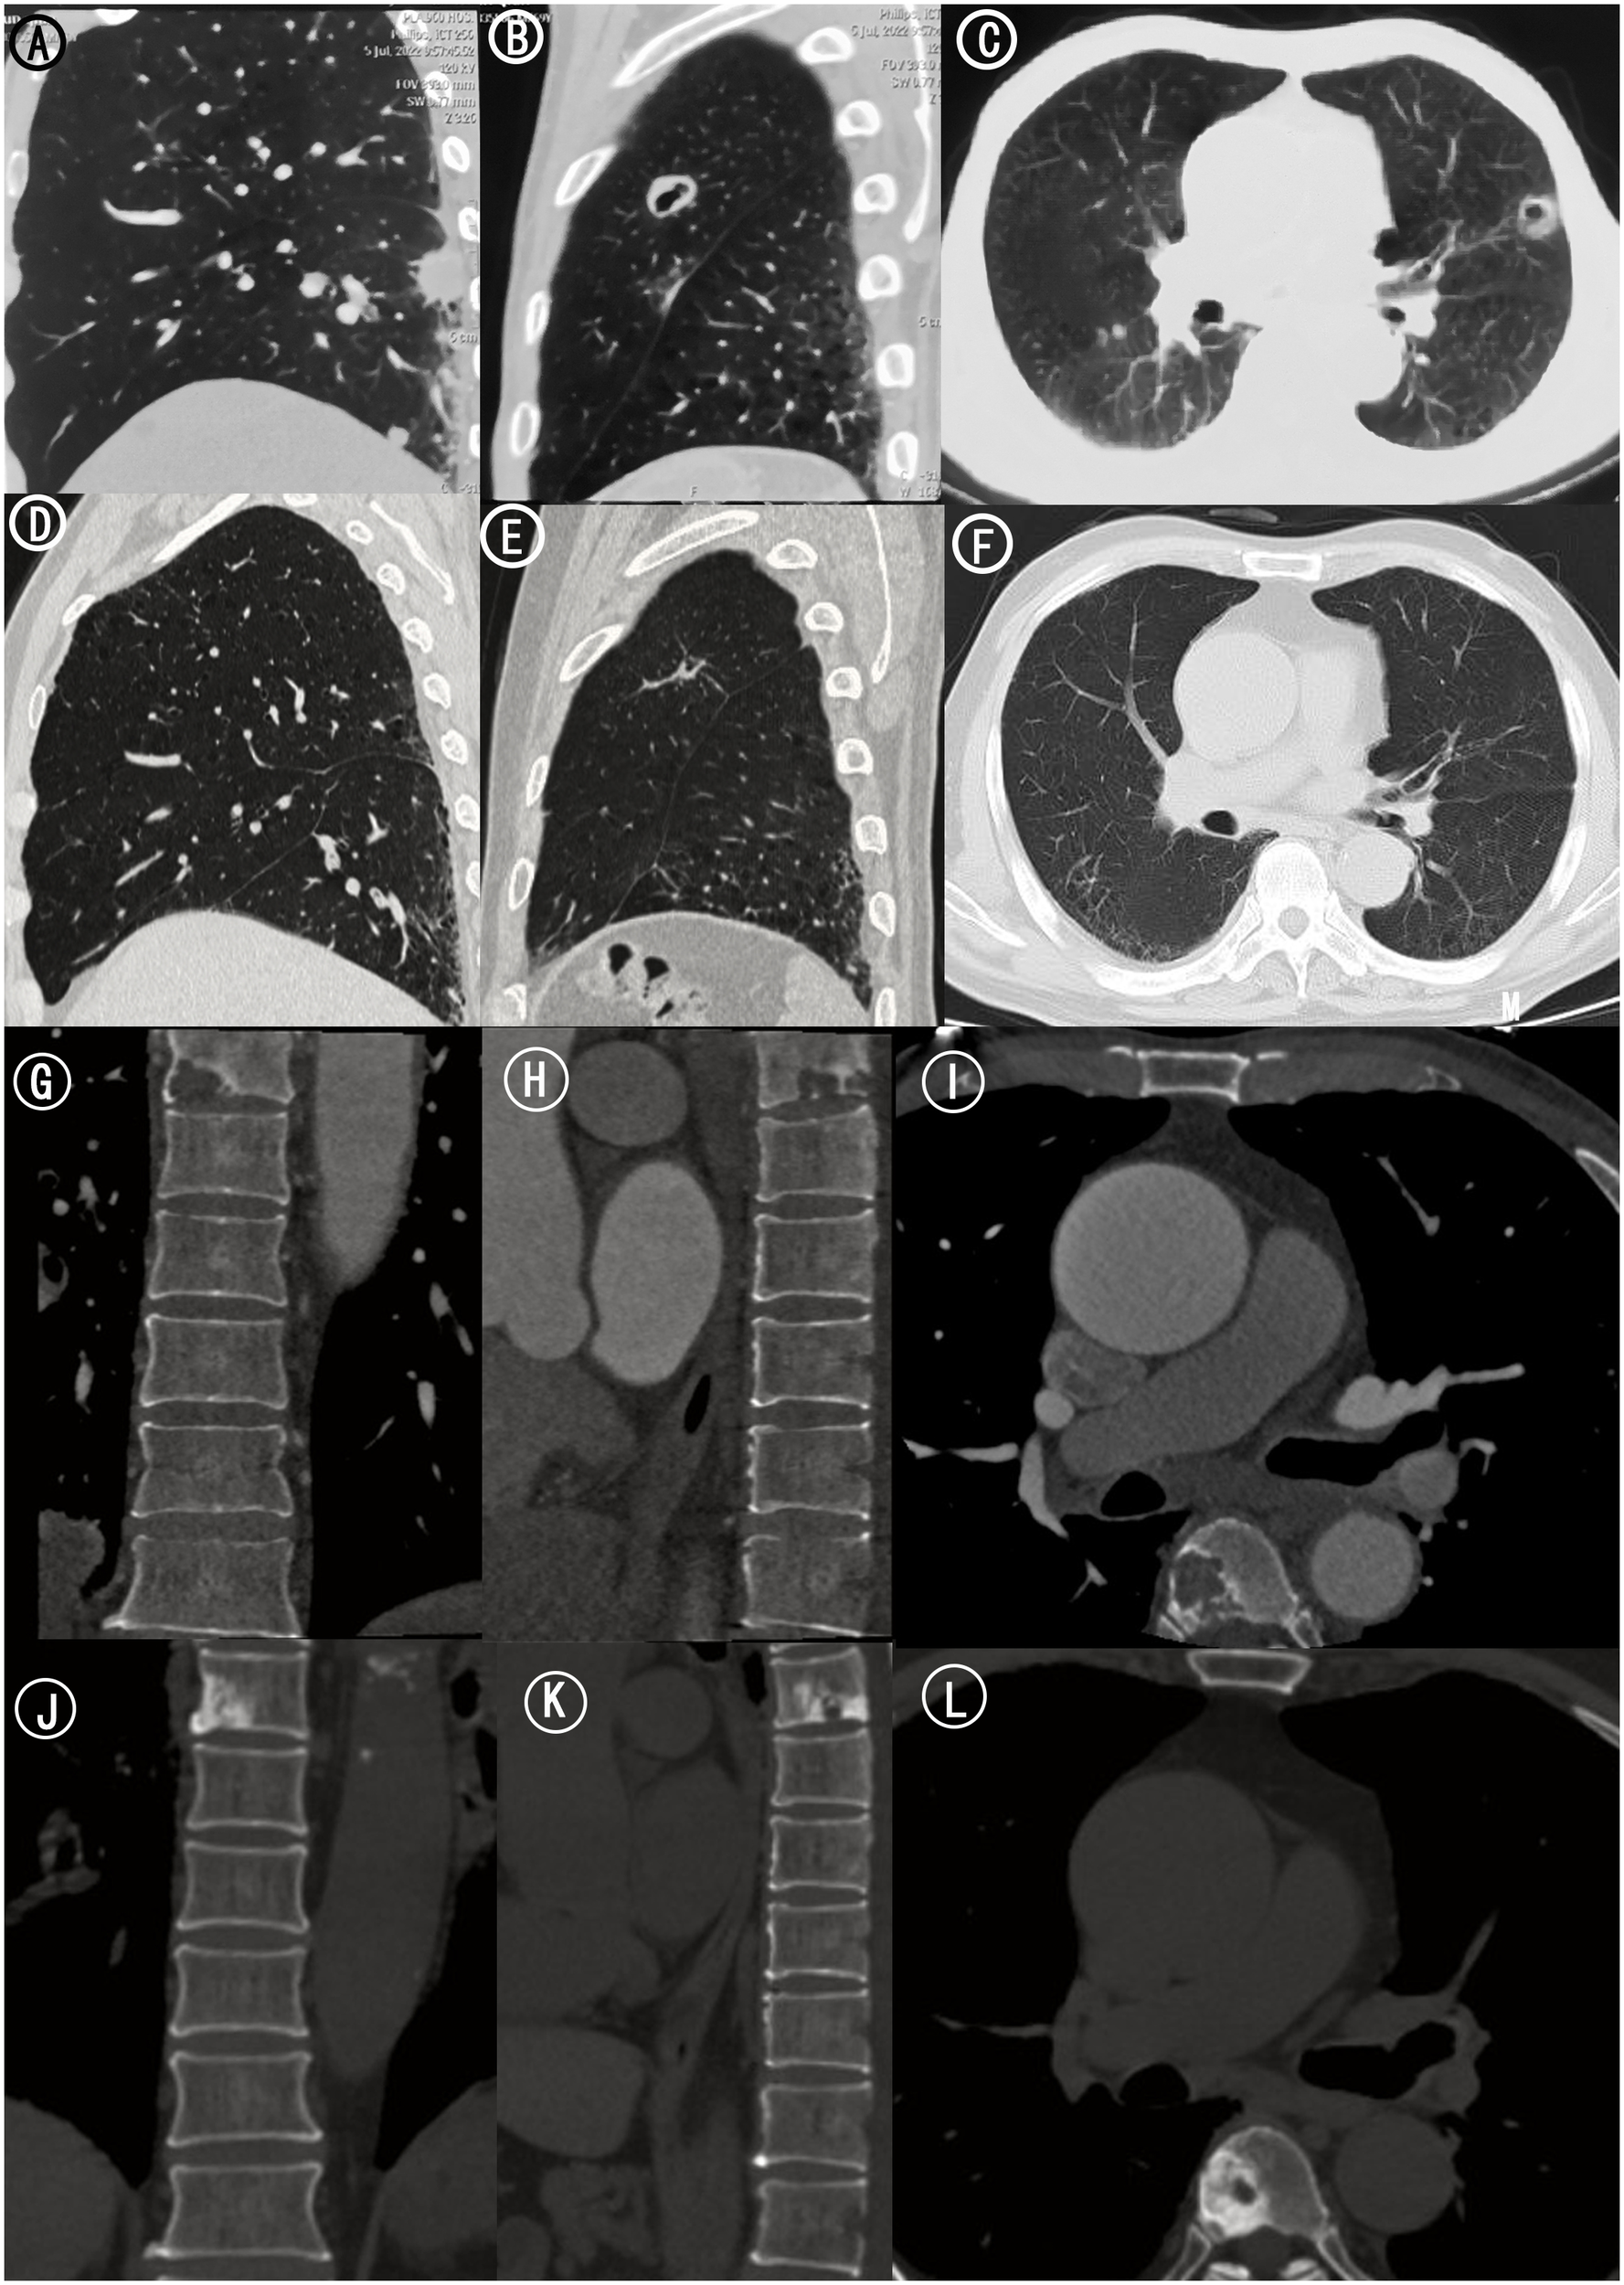

On June 27, 2022, the patient underwent computed tomography (CT) of pelvis and abdomen which revealed a bone destruction in thoracic six vertebra and left proximal femur (Figures 1, 2). Further evaluation of the lung using enhanced CT scan showed a pulmonary cavity (20 mm × 30 mm) in the superior lobe of left lung and scattered lung nodules, which was considered a possible malignancy with vascular invasion multiple metastatic sites (Figure 2). Femoral bone metastases were also found using emission computed tomography (ECT) and magnetic resonance imaging (MRI) (Figure 3). The multisystem neoplastic lesion was considered as multiple metastatic foci. No obvious abnormalities were observed in head MRI. Positron emission tomography (PET)- CT showed multiple pulmonary nodules in both lungs with increased fluorodeoxyglucose metabolism. The left proximal femur and thoracic six vertebra were hypermetabolic and metastasis to these sites was considered. The CT-guided percutaneous needle biopsy of the femur was performed on July 8, 2022. Microscopically, it showed the tumors were composed of spindle cells and epithelioid cells. Immunohistochemical staining showed TTF1(focal +), CK (+), CK8/18(+), Vimentin (+), CK7(+), EMA (+), TLE1(+), CD56(-), CD34(-), NapsinA (-), Desmin (-), P63(-), P40(-), S100(-), Ki67(+, about 50%) (Figure 4). The features were consistent with PSC.

Figure 2

Chest and Thoracic CT. (A) Sagittal CT scan of left lung. Scattered lung nodules were seen. (B) Sagittal CT scan of left lung. (C) Axial CT scan of bilateral lungs. A pulmonary cavity (20 mm × 30 mm) in the superior lobe of left lung. (D) Sagittal CT scan of left lung 15 months after treatments. The scattered lung nodules were significantly smaller than before. (E) Sagittal CT scan of left lung 15 months after treatments. (F) Axial CT scan of bilateral lungs 15 months after treatments. The left lung cavity was further reduced in size of approximately 16*0.9mm. (G) Coronal CT scan of thoracic vertebra. (H) Sagittal CT scan of thoracic vertebra. (I) Axial CT scan of thoracic vertebra. Bone destruction in thoracic six vertebra. (J) Coronal CT scan of thoracic vertebra 15 months after treatments. (K) Sagittal CT scan of thoracic vertebra 15 months after treatments. (L) Axial CT scan of thoracic vertebra 15 months after treatments. There were signs of a circular hyperdense shadow on the right side of thoracic six vertebra.

Since then, the regimen of anlotinib 12 mg orally quaque die(qd) from day 1 to 14 combined with sintilimab 200 mg on day 1 every 3 weeks has been maintained. The latest postoperative follow up to our hospital was on December 27, 2023(15 months after treatments), during which the chest-abdomen-pelvis CT showed that the left lung cavity was further reduced in size of approximately 16*0.9mm with scattered foci of fibrosis and focal inflammation in both lungs. The scattered lung nodules were also significantly smaller than before (Figure 2). The range of vertebral body destruction which showed a circular hyperdense shadow on the right side of thoracic six vertebra was not significantly changed (Figure 2). No signs of new metastasis and significant abnormalities were found in the original proximal femoral tumor site and other vertebral bodies.